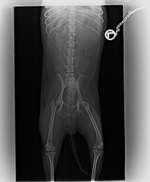

Hallo zusammen, meine Kleene hatte seit letztem Samstag eine Schwellung am Bein mit fühlbar festem Kern (rot=Schrotkugel), bin zum Doc, es wurde geröntgt, Bild anbei. Beim Röntgenbild wurde dann ein alter unverheilter Bruch (blau) sichtbar. Sie hat keine ersichtlichen Schmerzen wie bsp. humpeln, sie ...